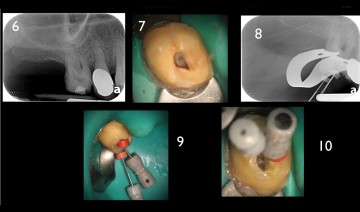

Initial x-ray, opening of the access cavity and x-ray with scouting file in the MB1 and MB2. The mineralization of the root canal entrance constrains the initial scouting.

The flaring instrument One Flare eliminates the first millimeters of the pulp parenchyma, thus reducing the stress on the files which are realigned in the root canal, in order to facilitate the access to and the shaping at the apical preparation limit.

The reasoned preparation of the root canal entrance with the flaring instrument One Flare allows for safe endodontic shaping and cleaning while preserving the root canal’s homothety.